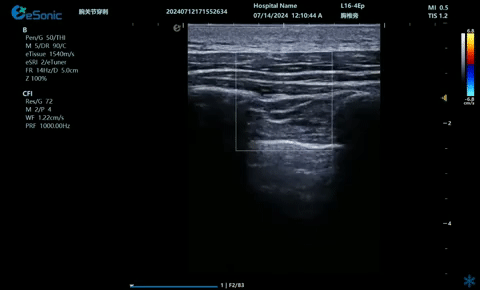

03

超声引导硬膜外麻醉-小等号

管内麻醉

9.2.gif